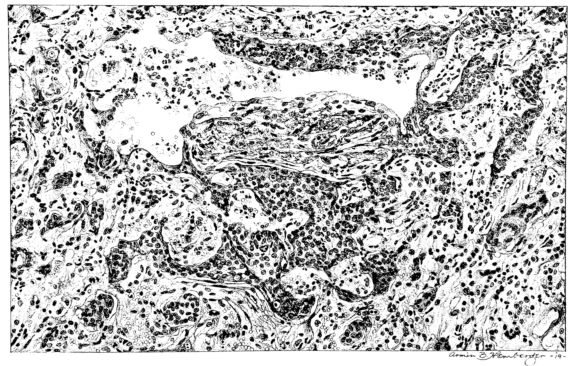

Microscopic examination of the lung showed the alveoli filled with an acute inflammatory exudate in many stages of degeneration and hyalinization (Fig. XLII). Abscesses were frequent, but were for the most part small. A similar necrotic mass was contained in the bronchi. There were, however, features of the microscopic picture that outweighed those already described. The alveolar and bronchiolar exudates were everywhere being invaded by a young granulation tissue, rich in fibroblasts and capillaries. Mononuclear cells abounded in the new tissue. Even more striking than the mesodermal new growth was the epithelial proliferation which could be seen in many areas. It not only attempted to cover the denuded bronchial surfaces, but stretched over masses of exudate and granulation in the lumina and extended in tongue-like projections for a considerable distance into the surrounding lung tissue (Fig. XLVIII).

These two examples differ widely in the distribution of the pulmonary involvement. They show the acute inflammatory process persisting and complicating the attempt at repair, which manifests itself, not only by the formation of granulation tissue, but also by extensive epithelial proliferation.